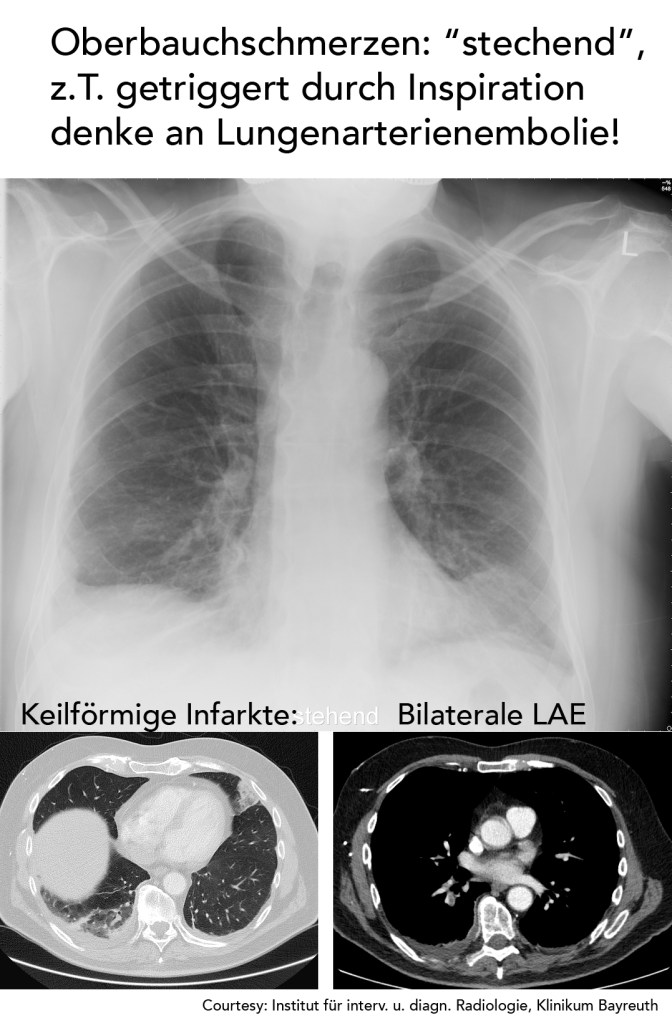

27-pleuritischer-bauchschmerz-pearl-de